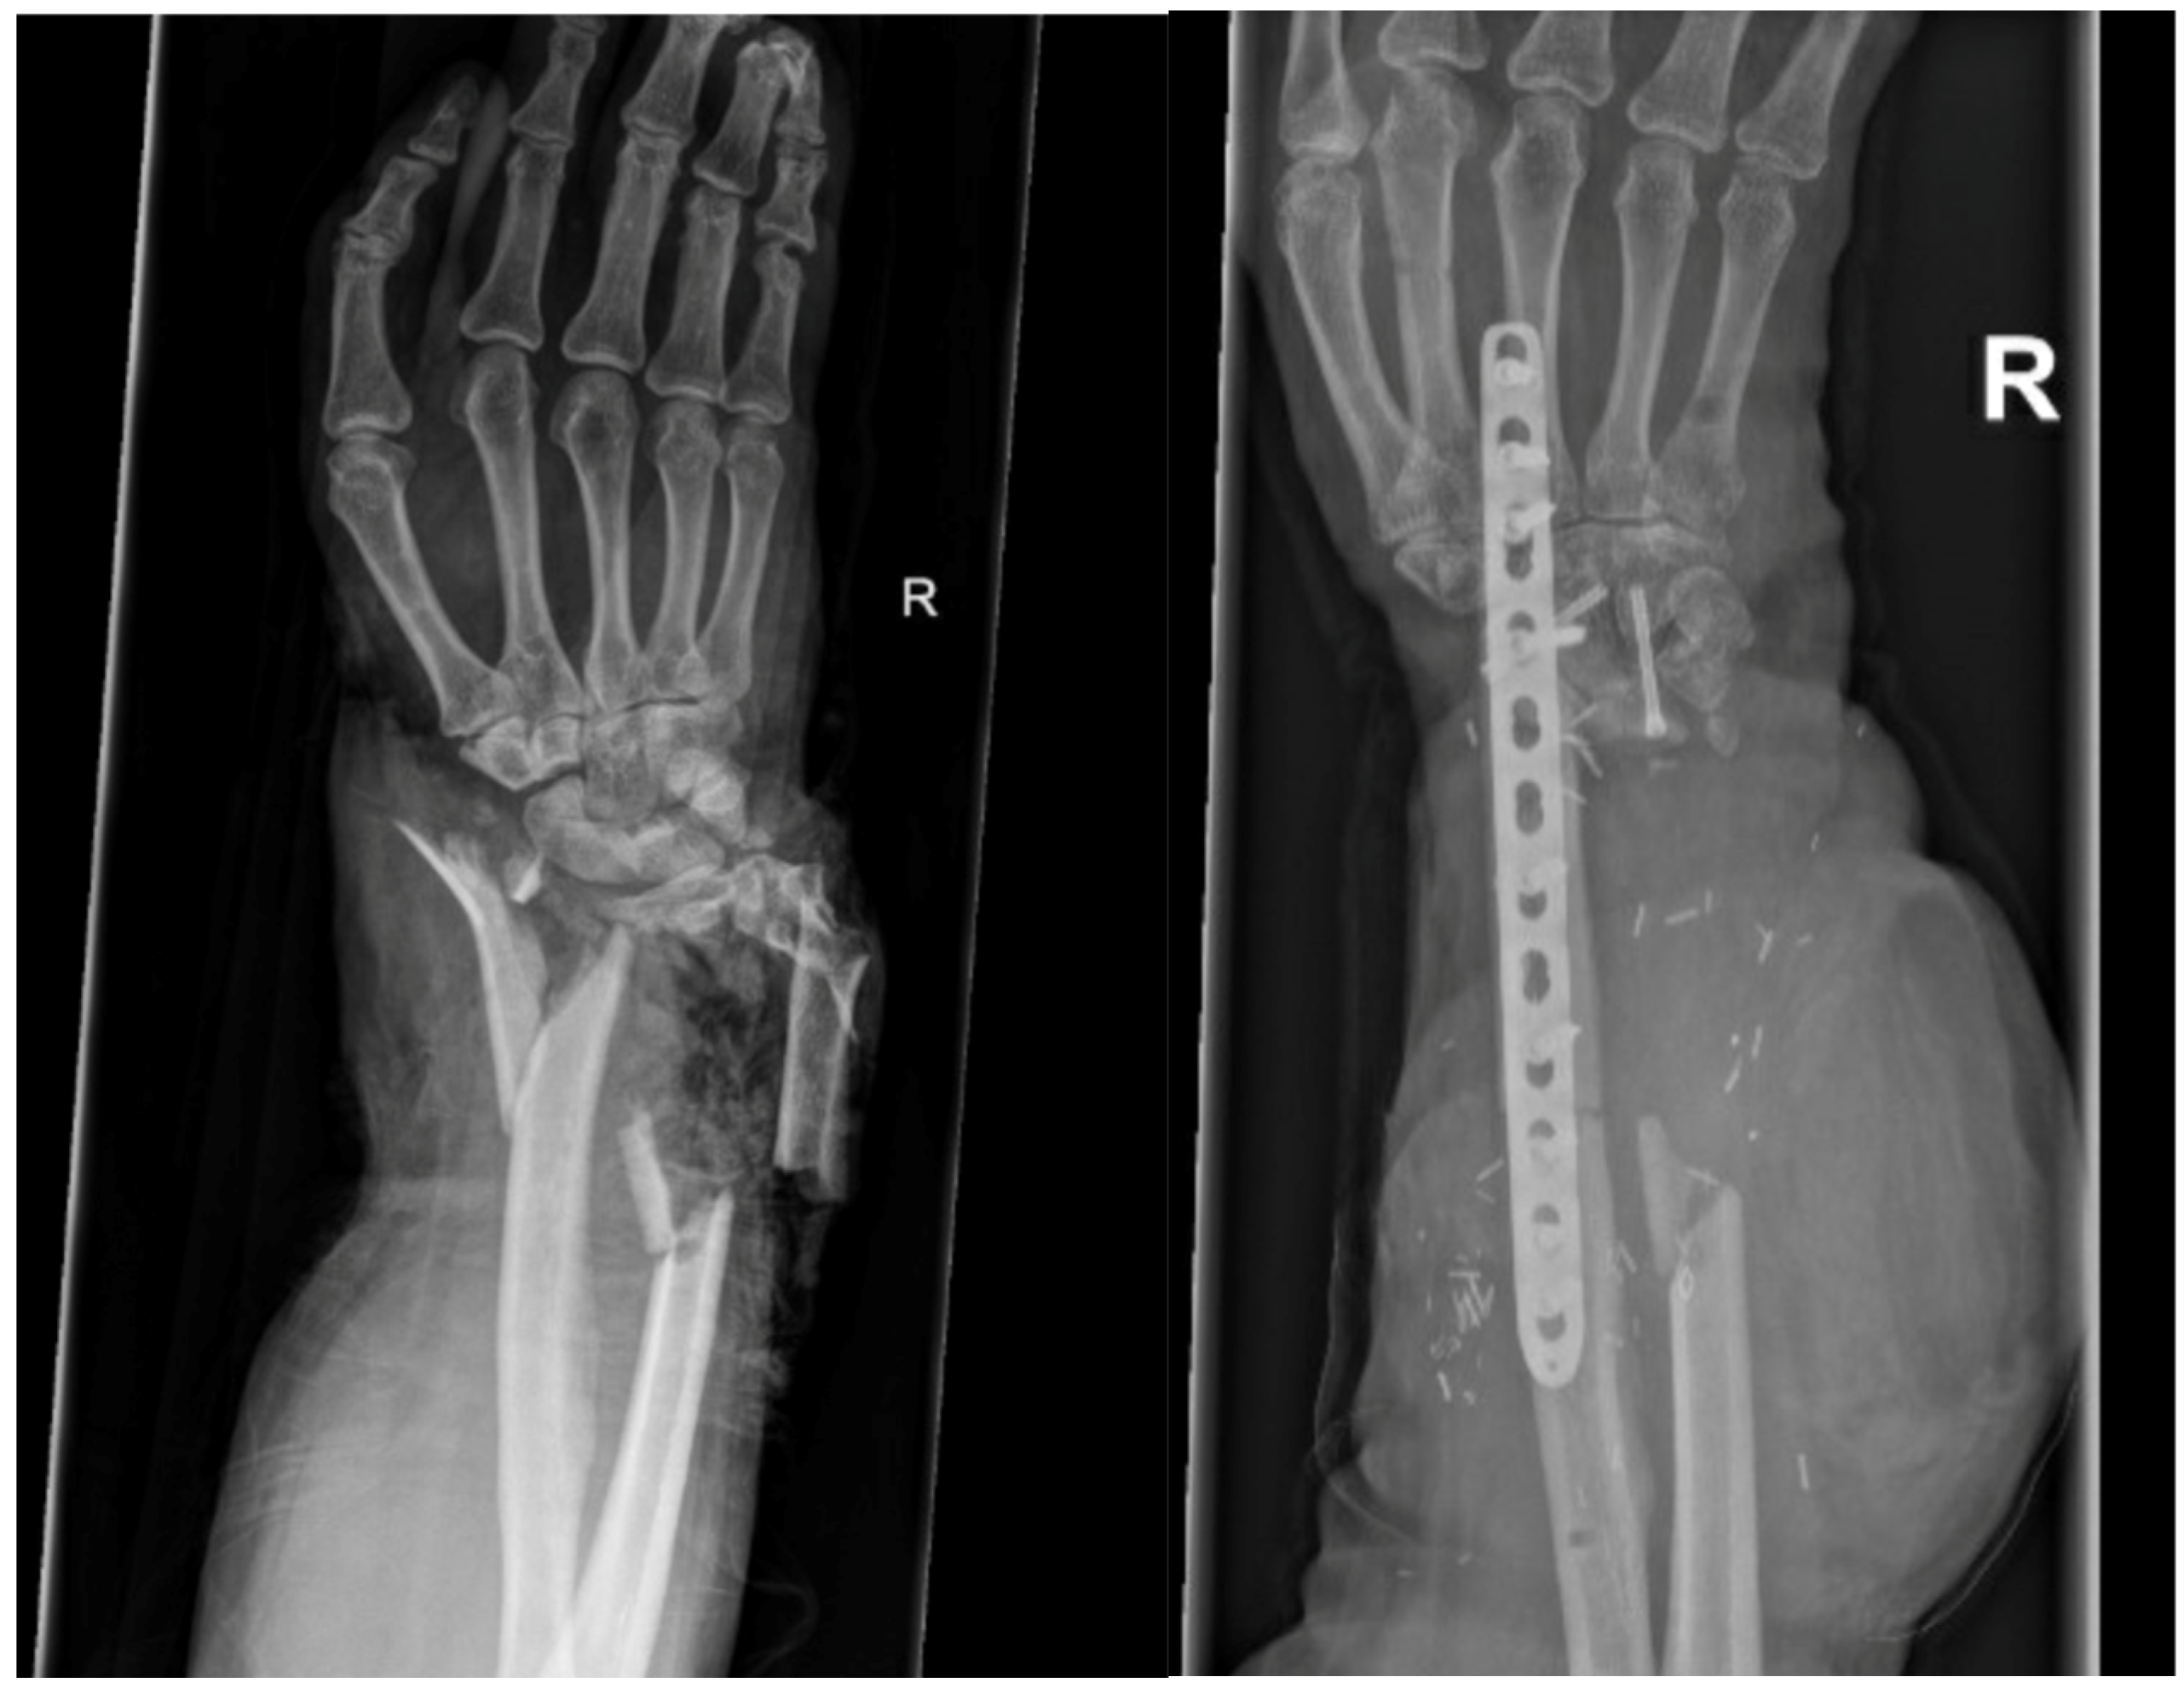

Arthrodesis of the Wrist with Vascularized Fibula Flap for the Treatment of a Large Defect of the Distal Radius

| GROUP 1 | Case 1 | Distal radius, parts of the proximal wrist | Trauma | 6 month | 32 | 9 cm | Vascularized fibula | Wrist arthrodesis | N/A N/A | 0-0-0° 40-0-50° | 60% | MMWS = 50 DASH = 24 | yes |